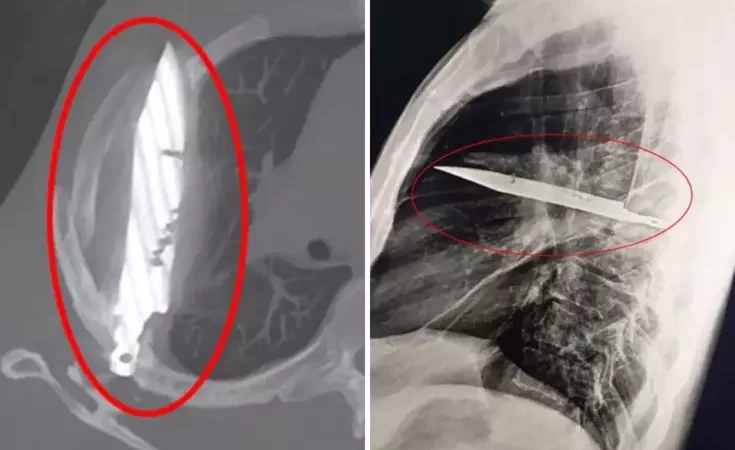

Göğüs ağrısıyla hastaneye gitti, göğsünde 8 yıldır bıçakla yaşadığı ortaya çıktı!

Tanzanya'da 44 yaşındaki bir adam, sağ memesinin altından iltihap akması şikâyetiyle hastaneye gitti. Doktorlar ilk muayenede herhangi bir ağrı, nefes darlığı, öksürük ya da ateş bulgusuna rastlamadı. Ancak yapılan röntgen, herkesin ağzını açık bıraktı: Adamın göğsünde tam sekiz yıldır saplı...